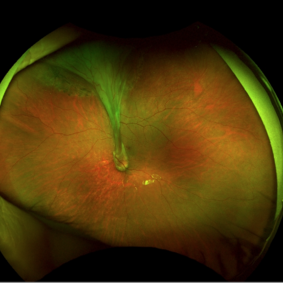

Familial Exsudative Vitreoretinopathy (FEVR)

Aug 4 2017 by Alexandre Grandinetti, MD, PhD

Fundus photograph of a 16-year-old monocular girl with FEVR.

Photographer: Corina Shrzek

Imaging device: P200DTX California - Optos

Condition/keywords: familial exudative vitreoretinopathy (FEVR)